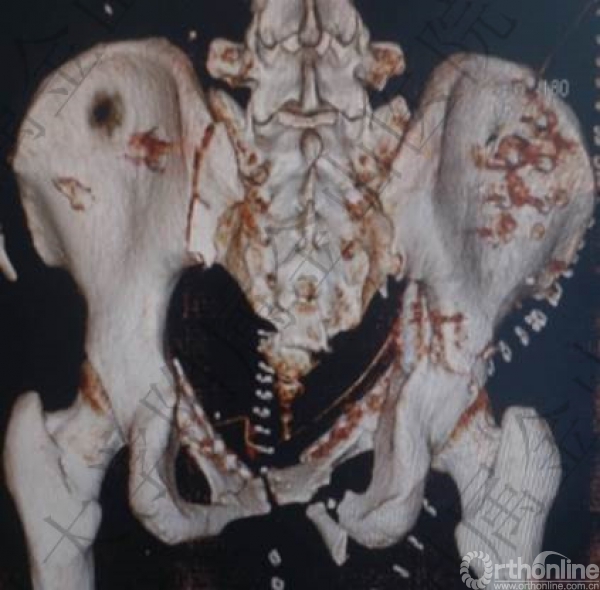

头胸腹CT未见明显实质脏器损伤,骨盆多发骨折:右侧髋臼骨折(双柱)。

骨盆骨折(C2)

2.骨盆多发骨折:右侧髋臼骨折(双柱)骨盆骨折(C2)(失血最主要原因);

1.髋臼双柱骨折经典入路:漂浮体位的前后联合

2.矛盾:后路?左侧骶髂关节内固定会移位吗?

3.前路?能不能同时固定右侧髋臼后柱?

髂嵴入路+Stoppa入路

手术效果(术后1周)